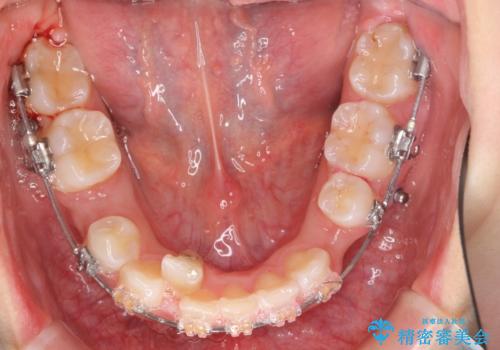

- 矯正装置

- プラスチックブラケット

奥歯のかみ合わせもずれていたため、上の奥歯を後ろに下げる処置をミニスクリューを用いて行いました。